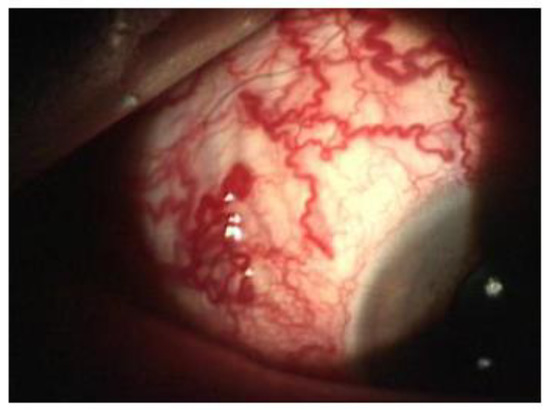

A 65-year-old woman presented to our attention complaining of two days of swelling in the right eye, reduced visual acuity, diplopia, and mild pain. The history was negative for recent trauma and confirmed good general health conditions. The physical examination revealed complete ophthalmoplegia (Figure 1), non-pulsatile reducible axile exophthalmos, eyelid edema, significant chemosis, and conjunctival ectropion (Figure 2). Visual acuity at the time of admission was 5/10 in the right eye and 10/10 in the left eye. The biomicroscopic examination of the anterior segment showed an important stasis of the episcleral vessels (Figure 3) and a shallow anterior chamber, whereas the fellow eye was unremarkable.

Figure 3. Dilatation of the episcleral vessels.